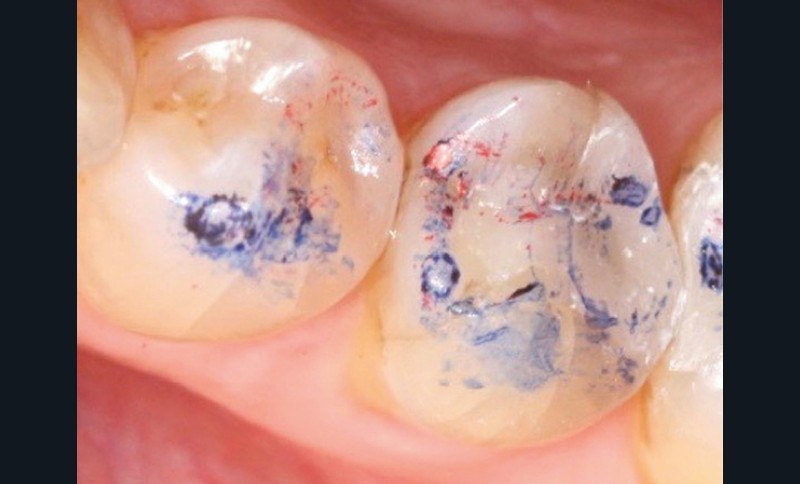

À chaque étape, le contrôle de l’occlusion est réalisé par technique du double marquage des points d’occlusion. Cette technique se base sur l’utilisation successive de deux marqueurs de teintes et d’épaisseurs différentes (40 µm et 8 µm). La superposition des marques permet de comparer et d’affiner l’analyse occlusale (fig. 1).